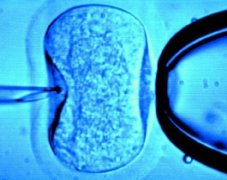

子宫腹侧为膀胱,其间上部隔有子宫膀胱凹,下部隔有子宫膀胱隔;背侧为直肠,其间上部隔有直肠子宫凹,下部隔有直肠子宫隔。两侧为韧带,其上部为宽大的子宫阔韧带及子宫圆韧带,下部为子宫主韧带及其向前后伸延的骶子宫韧带和耻骨子宫韧带。

子宫阔韧带:的上缘内含输卵管,其内端连于子宫角,外端于卵巢悬韧带相续;下缘附着于盆底,有子宫动脉由外向内及输尿管在其下方由后向前相互交叉走行;外侧缘附着于盆侧壁;内侧缘附着于子宫体侧缘,子宫动脉沿此缘迂曲上行;其前层包裹子宫圆韧带;后层包裹卵巢及其固有韧带。